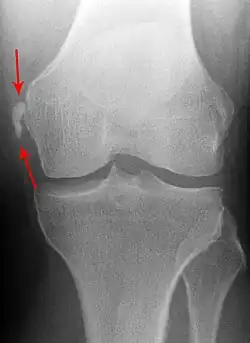

Pellegrini-Stieda syndrome. Also visible is a fracture of the patella.

Diagnosis is typically made on radiographs demonstrating the Pellegrini-Stieda syndrome sign accompanied by pain or restriction of range-of-motion of the knee joint.[2] Pellegrini-Stieda syndrome sign is typically described by a longitudinally linear opacity, which is a process that is describes characteristic of calcification in the soft tissue located medial to the medial femoral condyle.[2] This calcification seen on imaging represents the ossification of the medial collateral ligament, which typically does not develop until approximately three weeks after the initial injury.[2]It is important to note to distinguish this radiographic finding from that of a medial femoral condyle avulsion fracture, which is an injury in which a pulling force of a tendon or ligament fractures away a piece of the bone from its attachment site.[2]